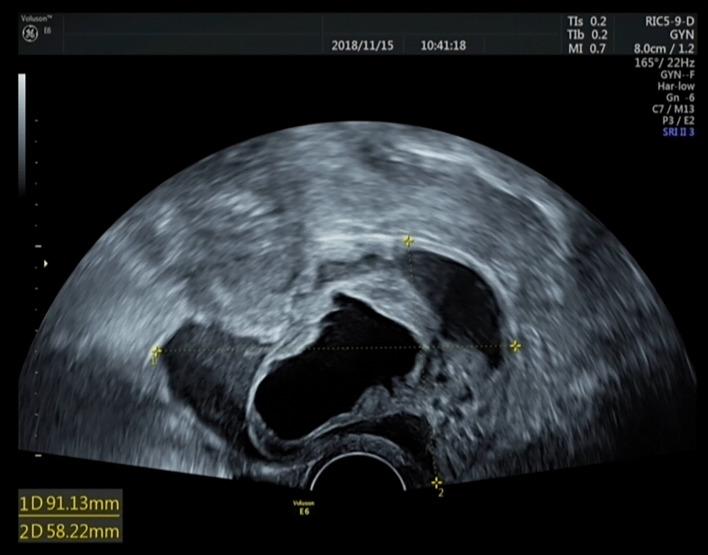

Uterine cervical Müllerian adenosarcoma (MA), a rare malignant tumor of the female reproductive organs, is composed of a benign epithelium and a low-grade malignant stromal component. Because few studies have investigated the clinical management of MA, misdiagnosis often occur. Therefore, we proposed an optimal course of clinical management for patients with MA. MA is possibly a malignant transformation of the cystadenofibroma. In this study, we present a case of a 46-year-old woman who presented with symptoms of MA of the uterine cervix, such as metrorrhagia and a cyst in the cervical canals, after transvaginal excision of the left ovarian mucinous cystadenofibroma.

子宫颈苗勒管腺肉瘤(MA)是一种罕见的女性生殖器官恶性肿瘤,由良性上皮和低级别恶性间质成分组成。由于很少有研究探讨MA的临床管理,因此误诊经常发生。因此,我们提出了MA患者的最佳临床管理方案。MA可能是囊腺纤维瘤的恶性转化。在本研究中,我们报告了一例46岁女性病例,该患者在经阴道切除左侧卵巢黏液性囊腺纤维瘤后,出现了子宫颈MA的症状,如子宫出血和宫颈管囊肿。